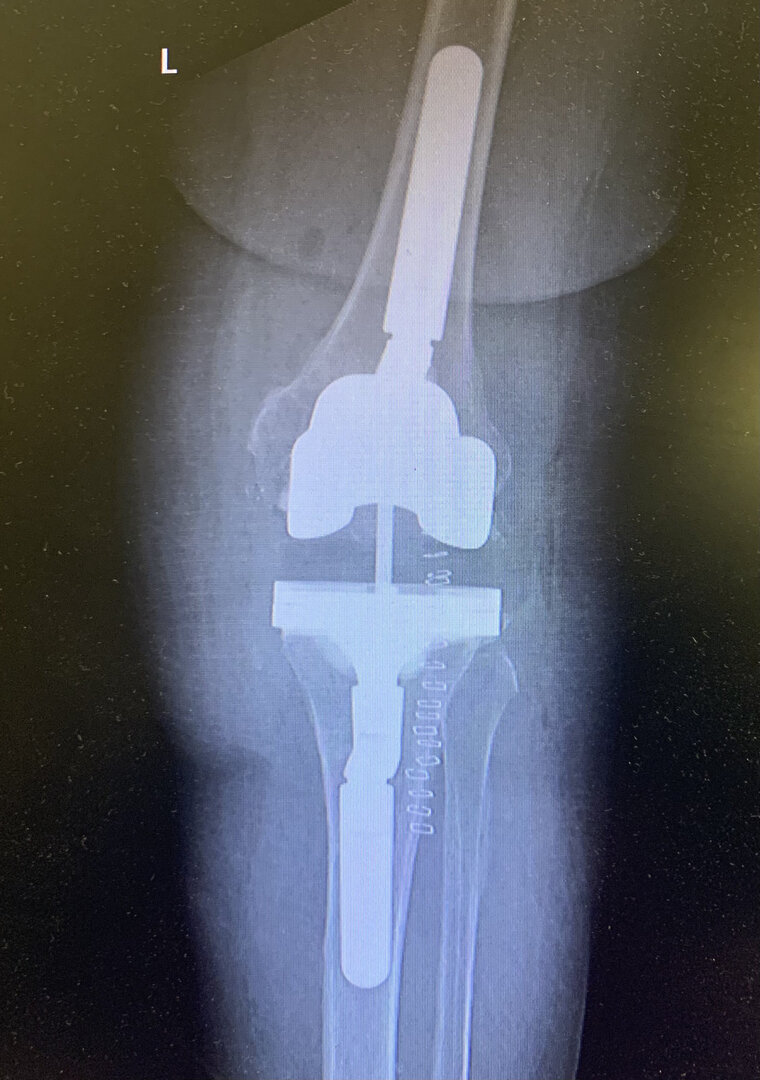

Aşınmış, hasar görmüş ya da eklem yüzeyleri tamamen bozulmuş diz ekleminin, yapay bir eklemle değiştirme işlemidir. Ameliyatta, ağrıya neden olan hasarlı kemik ve kıkırdak dokular çıkarılarak; yerine metal ve özel plastikten yapılmış, uzun ömürlü bir protez yerleştirilir. Bu sayede diz, tekrar ağrısız ve stabil bir şekilde çalışır hale gelir.

Eklem yüzeyleri özel kılavuzlar yardımı ile temizlendikten sonra metal protez eklem yüzeylerine bir kemik çimentosu ile adapte diyoruz. Bu iki metal yüzeyin sürtünmesini azaltmak için polietilenden yapılmış özel bir plastik tabakayı sisteme dahil ediyoruz.